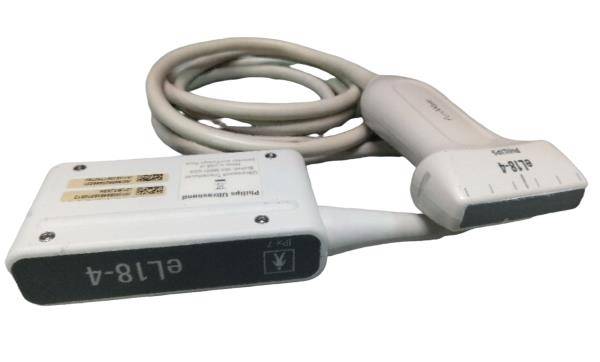

One of the standout features of the TFT LCD Digital Laptop Linear Array Ultrasound Scanner is its linear array probe. This probe is known for its high-frequency linear transducer, which is ideal for scanning small and superficial structures like tendons, arteries, and veins, so it offers precise imaging capabilities. The linear array also supports a range of applications such as musculoskeletal, emergency medicine, and vascular imaging.